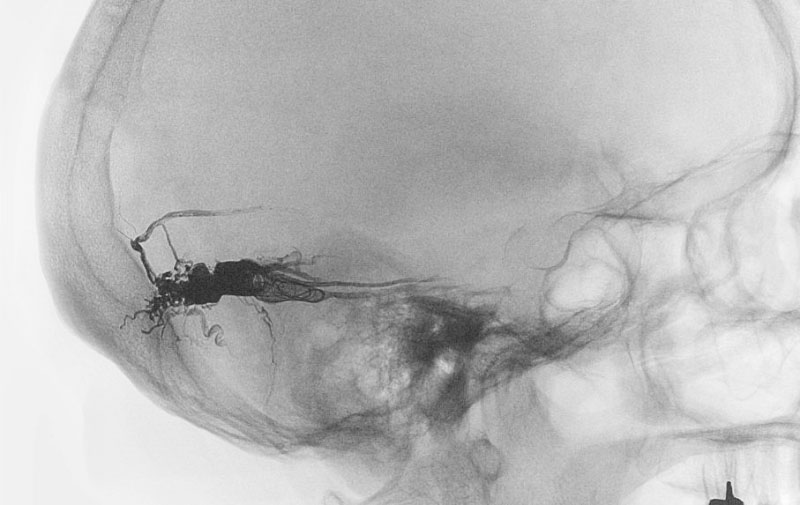

右円蓋部髄膜腫

40代

大阪府の病院

No.1598 手術前

No.1598 手術中

No.1598 手術後